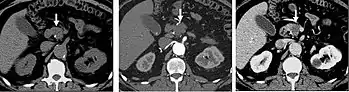

Detection and characterization of renal parenchymal masses is a frequent indication for CT. An initial noncontrast CT is important for detecting calcium or fat in a lesion, and to provide baseline attenuation of any renal masses. Following noncontrast scanning, intravenous contrast is injected and a corticomedullary phase is obtained at approximately 70 seconds (figure 7a, 7b). The corticomedullary phase is characterized by enhancement of the renal cortex as well as the renal vasculature. This phase is valuable in the evaluation of benign renal variants, lymphadenopathy and vasculature, however certain medullary renal masses may not be visible during this phase due to minimal enhancement of the medulla and collecting system. The parenchymal phase is obtained approximately 100-200 seconds after the injection of contrast material (figure 7c). Parenchymal phase imaging demonstrates continued enhancement of the cortex, enhancement of the medulla, and various levels of contrast material in the collecting system. The parenchymal phase is highly important for the detection and characterization of renal masses, parenchymal abnormalities, and the renal collecting system. This method of imaging does not evaluate for abnormalities of the collecting system.

Common renal masses can occasionally be differentiated from each other using this imaging technique. Renal cell carcinomas and oncocytomas typically demonstrate intense heterogeneous enhancement on the parenchymal phase images and cannot be reliably differentiated from each other but can be distinguished from other renal masses. Angiomyolipomas (AML’s) also demonstrate intense contrast enhancement but characteristically contain macroscopic fat which can be detected on the noncontrast images, and can help to differentiate AML’s from renal cell carcinomas and oncocytomas. Renal lymphoma on the other hand, will often have decreased enhancement when compared to the renal parenchyma on the parenchymal phase images.

FIGURE 7. Selected images from a renal mass specific protocol CT. Corticomedullary phase (axial 7a) demonstrates peripheral enhancement of the renal cortex with minimal opacification of the renal medulla. There is a large renal cell carcinoma in the left kidney (right in image) which can be differentiated from the normal renal parenchyma by the heterogeneous and differential enhancement. The renal artery and vein are opacified in this phase as well. The collecting system is not opacified (coronal reformat 7b). In the parenchymal phase, the renal cortex and the medulla are enhancing. The renal cell carcinoma in the left kidney is not as well defined when compared to the corticomedullary phase images, but is actually slightly more conspicuous. There is some contrast noted within the collecting system during this phase (7c).